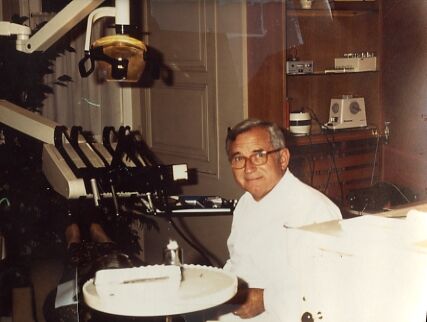

1️⃣ Vous êtes Omnipraticien Vous soignez un patient, et vous avez un mal de chien à prendre une empreinte sur la 37. Elle refoule votre miroir et votre porte-empreinte… …